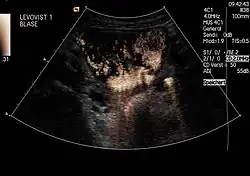

Kontrastmittel in der Harnblase mit Reflux in den linken Harnleiter

Kontrastmittel im Nierenbecken der linken Niere

Um einen Rückfluss (Reflux) von Urin aus der Blase in die Niere auszuschließen: Diese Untersuchung, genannt Miktionsurosonografie (MUS), kann die bisher durchgeführte Röntgenuntersuchung mit Kontrastmittel (Miktionscystourogramm, MCU) ersetzen. Auf diese Weise ist also eine Refluxprüfung ohne Strahlenbelastung möglich. Da die empfindlichen Gonaden bei der Röntgenuntersuchung regelmäßig mit im Nutzstrahlenbündel liegen, ist dies ein großer Vorteil.